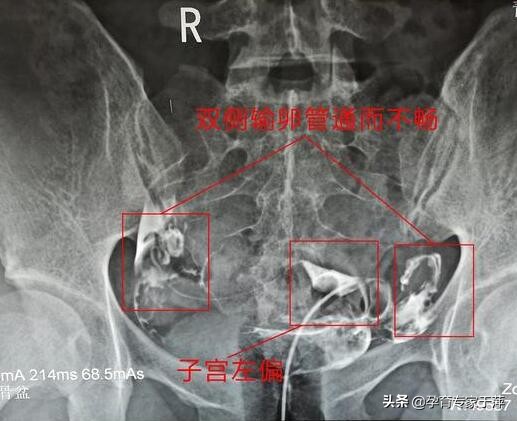

找到我就诊的时候,我重点查了多囊的情况,并建议她做输卵管造影,男方也查一下小蝌蚪。造影结果显示子宫左偏,双侧输卵管通而不畅。抽血内分泌FSH: 4.83 , LH: 3.39 , B超显示:双侧卵巢多囊样改变,监测排卵也没问题,根据患者自述,也没有月经不调的现象,每个月还算准时,周期也比较正常。男方精液检查无异常。最终确诊为:原发不孕,子宫左偏,双侧输卵管通而不畅。

重点来了:根据多囊卵巢综合征的诊断标准,这位患者并没有月经不调现象,排卵也正常,虽然B超检查双侧卵巢呈多囊样改变,但内分泌黄体生成素(LH)和促卵泡生成素(FSH)的指标并不典型,这并不影响怀孕,而且患者也没表现出明显的多囊卵巢综合征体征。所以,她的不孕问题主要是输卵管引起的。